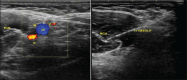

Background: The established methods of nerve location were based on either proper motor response on nerve stimulation (NS) or ultrasound guidance. In this prospective, randomised, observer-blinded study, we compared ultrasound guidance with NS for axillary brachial plexus block using 0.5% bupivacaine with the multiple injection techniques.

Methods: A total of 120 patients receiving axillary brachial plexus block with 0.5% bupivacaine, using a multiple injection technique, were randomly allocated to receive either NS (group NS, n = 60), or ultrasound guidance (group US, n = 60) for nerve location. A blinded observer recorded the onset of sensory and motor blocks, skin punctures, needle redirections, procedure-related pain and patient satisfaction.

Figures